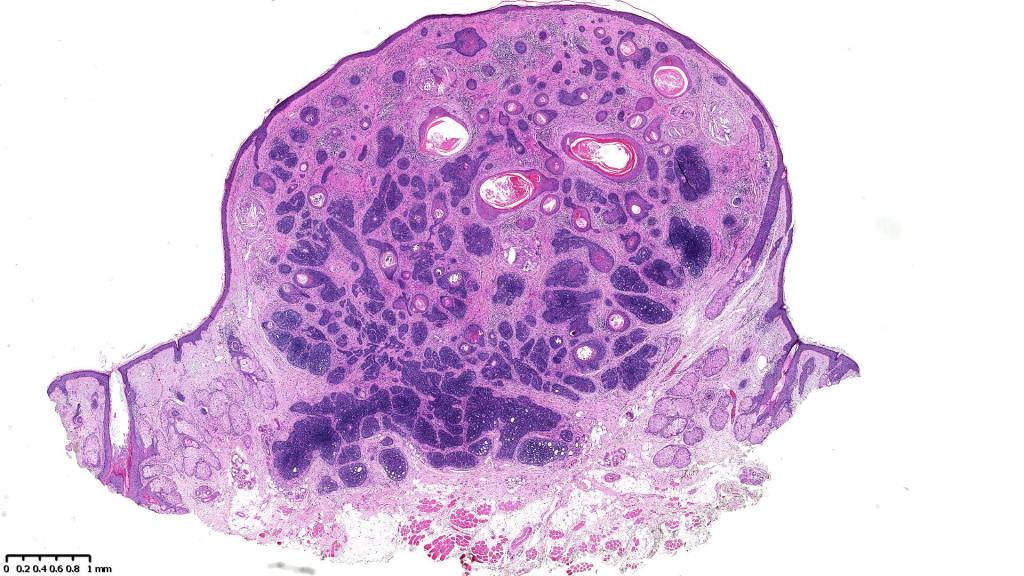

The entities trichoblastic fibroma, trichogenic trichoblastoma, giant solitary trichoepithelioma, subcutaneous trichoepithelioma, immature trichoepithelioma are all included under the rubric trichoblastoma. Trichoblastoma shared many histological similarites with trichoepithelioma but differs by its much larger size, extension into the deep dermis/subcutaneous fat or deeper and large circumscribed nodules Papillary mesenchymal bodies are often absent or more difficult to identify. The distinction is important as trichoblastoma is not syndromic.

•Sharply circumscribed, unencapsulated nodule in deep dermis +/- subcutaneous fat or deeper (trichoepithelioma is much more superficial)

•Variably sized but generally large, basophilic tumor nodules composed of small uniform basaloid cells with minimal cytoplasm

•Variable keratocysts

•A rich fibromyxoid mesenchymal stroma with variable papillary mesenchymal bodies (sometimes these are absent)